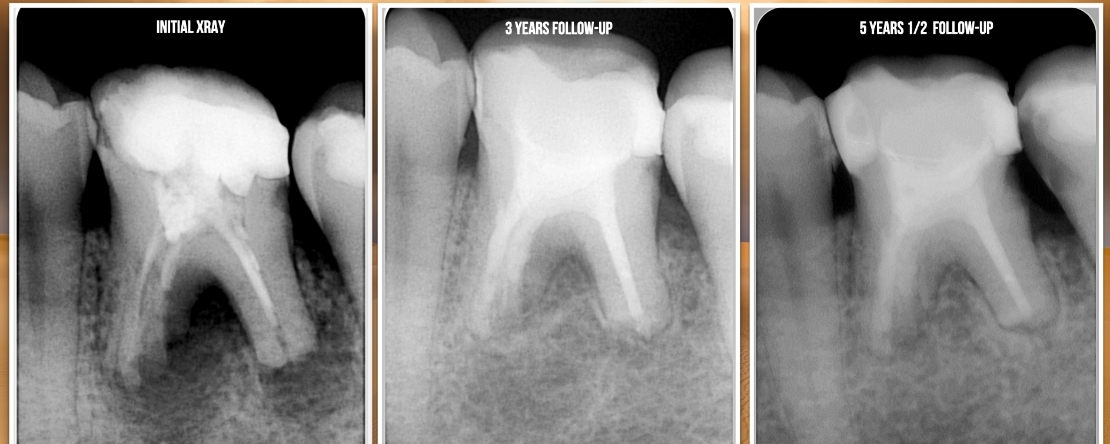

O tratamento endodôntico é um procedimento previsível com uma elevada taxas de sucesso.

O sucesso depende de vários fatores, que vão desde uma instrumentação que respeite a anatomia interna evitando a ocorrência de eventos iatrogénicos, uma irrigação adequada e consequente redução da carga bacteriana do espaço intra-canalar e um adequado selamento do espaço interno, com a obturação e “selamente” coronário com uma adequada restauração.

Com esta apresentação pretendemos refletir nos aspectos que têm alterado nos últimos anos e qual o impacto que os mesmos têm no outcome do tratamento.